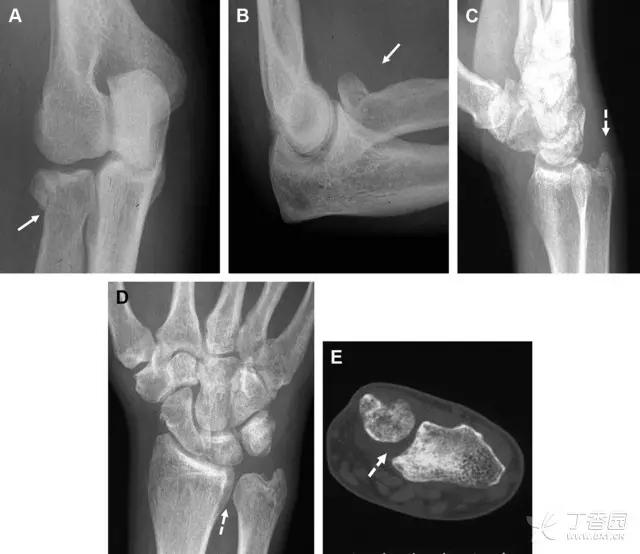

Essex-Lopresti 损伤。前后位(A)和侧位(B)示桡骨头关节内骨折(白色实线箭头);(C~E)伤后 1 个月复诊,患者诉腕关节疼痛,X 线(C,D)发现下尺桡关节脱位,(E)CT 进一步证实损伤的存在 (来源:Radiol Clin North Am. 2015 Jul;53(4):717-36)